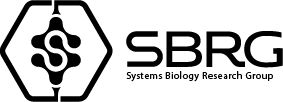

GEMMA: Elegant. Rational. Comprehensive.

The power of biomarkers has remained limited to binary evaluation of abnormal or normal of each individual biomarker. GEMMA analytics uses

the power of combinatorial algorithms and matrix analysis to go deeper, decrypting information found only in a multi-factorial approach. While

hundreds of studies have demonstrated the power of this approach, only GEMMA places the fruits of this research to clinical applications.

Consult with confidence

It’s time to start treating the patient who has the disease and not just the disease the patient has. GEMMA provides insightful information to customize treatments addressing the root cause of disease rather than simply suppressing symptoms. The right data leads to the right treatment.

The GEMMA advantage

GEMMA is the perfect complement to your existing approach to investigation.

GEMMA shows you more.

GEMMA provides a 360 degree approach by extracting information

from your current biomarker profile. GEMMA open the lense and gives

you more by creating a pathway to personalized evaluation and treatment.

Studies have shown that biomarkers can reveal more information about your patient’s disease state when they are

contextualized through ratios, e.g. Total/free testosterone, BUN/Creatinine, CD4/CD8, or Hematocrit (RBC/Hemoglobin).

GEMMA analytics combines hundreds of ratios through a complex analysis to provide context for you regarding the

internal state of your patient.

The key is following biomarker drift away from optimal values in dozens of biomarkers simultaneously and in relationship

to each other. Every GEMMA panel presents the original results and the augmented analysis to maintain standards of care

and evaluation in addition to the enhanced understanding that comes with GEMMA.

Longitudinally follow the augmented results to follow subtle trends indicating your patient’s response to interventions.

With numerical results, the patient can more easily appreciate indications of responsiveness even if symptoms are still

present but lessened. Having more treatment options allows for more opportunities to address insufficient responses

and refractory cases.

GEMMA: Panels

and evaluation types